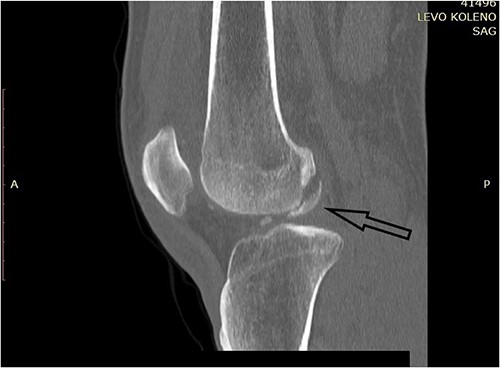

CT scan of the left knee (sagittal) with three fragments (arrows) and patellar fracture (arrowhead).

CT scan of the left knee (sagittal) focusing on the largest posterior fragment (arrow).

A plain X-ray of the left knee revealed a single defect of the lateral femoral condyle in the anteroposterior (AP) view. The lateral view showed a free bone fragment with a defect (Fig. 1A and B). Additional diagnostic imaging was performed. A computerized tomography (CT) scan revealed multifragmentary (three fragments) fracture of the lateral femoral condyle accompanied by a fracture of the left patella (Fig. 2). The fracture was classified as 33B3.2 according to the Association for Osteosynthesis–Orthopaedic Trauma Association (AO/OTA), Type II C (according to Letenneur) [2]. It was decided that single-approach surgery (posterior or anterior) would be insufficient for acceptable anatomic reduction and proper fixation of all the fragments because of the fracture complexity. The preoperative plan consisted of a posterior-first approach (extended posterior approach to the proximal tibia) for fixation of the largest (posterior) fragment (Fig. 3) followed by an arthroscopic anterior approach (for anterior fragment fixation). The predetermined time interval between the two procedures was to allow the healing of the joint capsule after the index surgery. Operative fixation of the patellar fracture was not indicated.